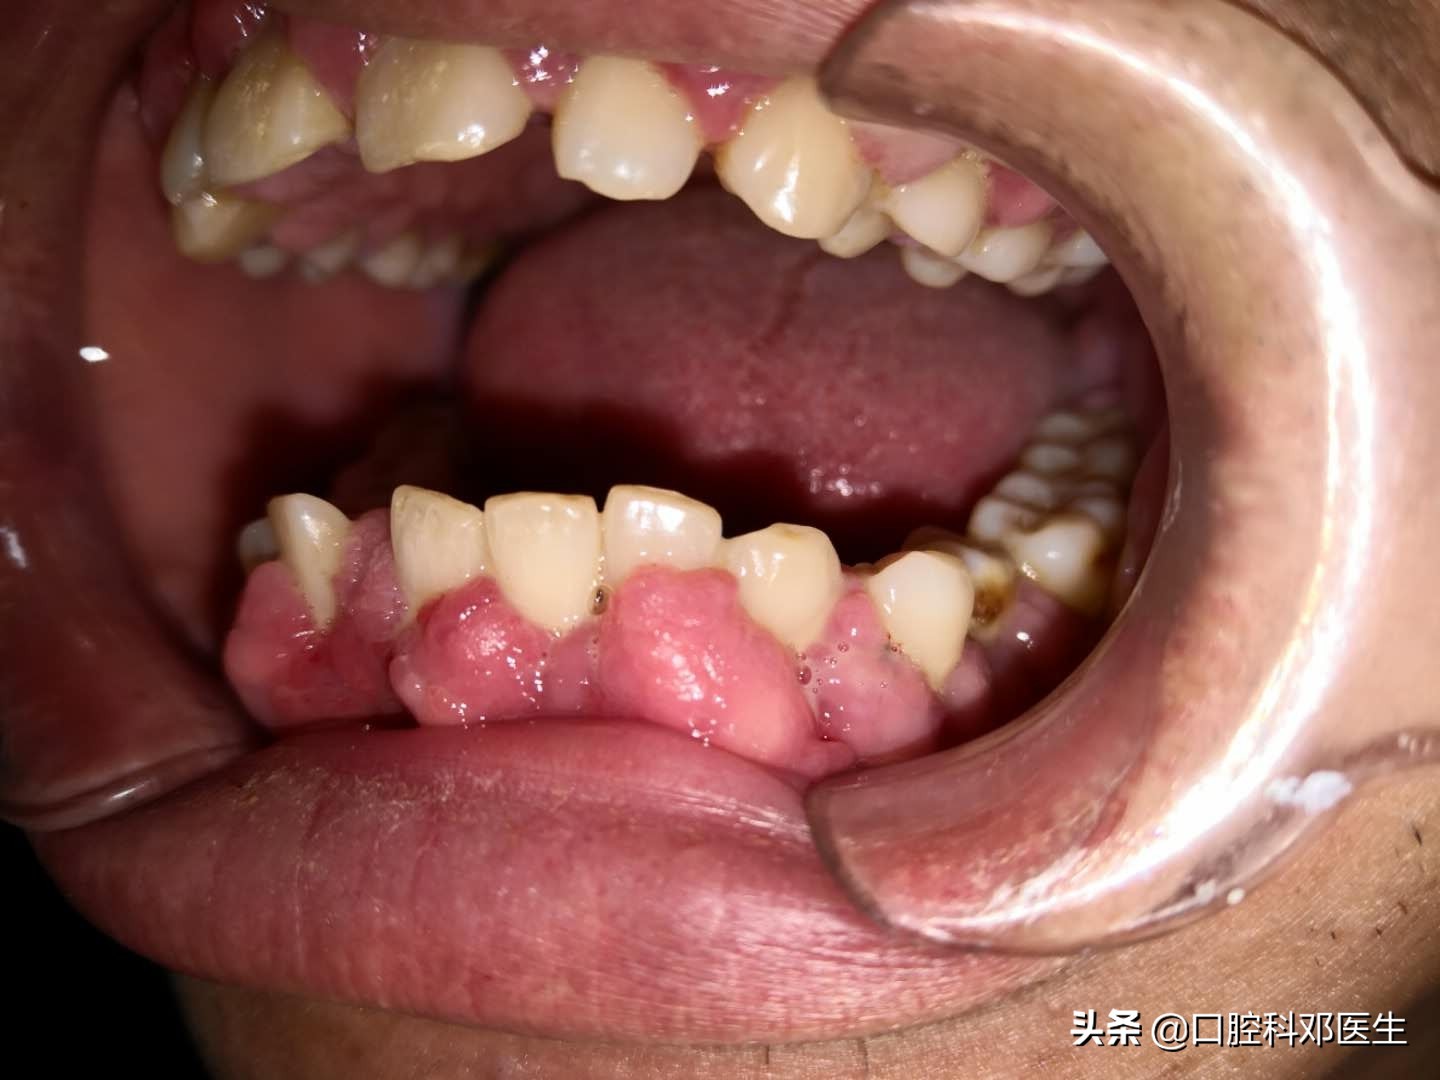

50岁的罗先生因全口牙龈肿胀呈球状,来到了我的门诊,他向我倾诉:这种现象有1年多,开始只有一点点,现在都长的有这么大啦,主要覆盖在牙齿的外面,平时也不痛也不痒,但是口臭比较明显,已经严重影响到我的工作生活,不敢张嘴说话,有时还合并有牙龈出血!

我检查了他的口腔,发现几乎全部牙齿的颊侧牙龈乳头呈球状、结节状增生,牙龈红,个别牙龈碰之容易出血,特别是上下门牙尤为明显。于是问了他的情况,原来他有高血压病,一直服用硝苯地平,这些症状正是服用药物1月后才慢慢出现的!

结合检查和他服用的药物,我判断这种牙龈增生就是药物性牙龈增生!

药物性牙龈增生是指长期服用某些药物而引起的牙龈的纤维性增生和体积增大。一般开始于服用药物后的1-6月内,增生的牙龈起于唇颊侧或舌腭侧牙龈,呈小球状突出于牙龈表面,逐渐扩大,并扩展到整个牙龈,严重的可覆盖大部或全部牙冠,常见于全口牙龈,以上下门牙区较重。